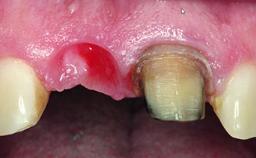

Replacement of a Missing Upper Left Central Incisor: Late Placement of an RC Bone Level Implant, CAD/CAM Zirconia Abutment

A healthy 37-year-old female patient was referred for a consultation on the replacement of missing tooth 21 with an implant-supported restoration. She stated that several years previously the tooth had been traumatically avulsed following a motor vehicle accident. The tooth was replaced with a three-unit fixed partial denture (FPD) immediately afterwards. Over time, she became disillusioned with the FPD and looked for a different option, including orthodontic therapy. She presented still in her orthodontic appliances, with the pontic sectioned free from the FPD but attached to the archwire. Her orthodontist felt that orthodontic treatment had been successfully completed, but nevertheless referred her before removing the appliances in case adjustments were necessary.

Bone Volume Deficient horizontally, allowing simultaneous augumentation

Soft Tissue Contour and Volume Slightly compromised